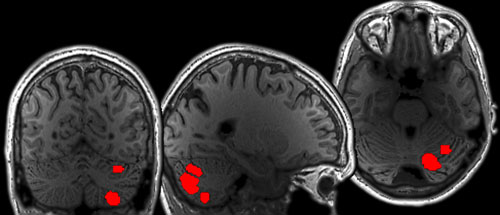

Three views of a gray brain scan with bright red spots on a black background

fMRI scans showing language regions of the cerebellum in a human brain. Areas in red highlight regions that reliably respond to language, viewed from the back (left), side (middle), and top (right) of the brain. Image: Colton Casto

The team found that four different regions in the cerebellum respond to language — but not all in the same way. One region responded solely to language, in a similar manner as language areas in the cerebral cortex. The remaining three regions responded to language but were also active during motor tasks, demanding nonlinguistic tasks, and/or the processing of meaningful visual stimuli.